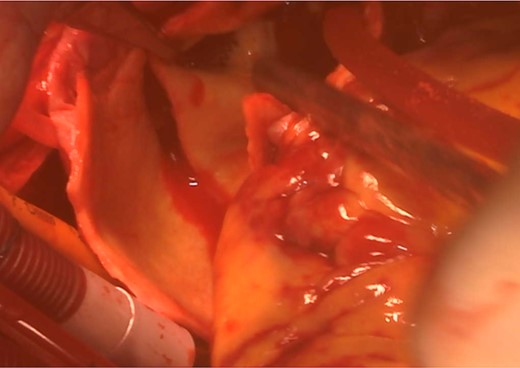

An 82-year-old woman with loss of consciousness was transferred to our institution. CT showed aortic dissection involving ascending aorta extending to the brachiocephalic artery where the true lumen was occluded due to the false lumen. The level of consciousness was getting improved during examination, then, the decision was made to proceed with performing central aortic repair first. Cardiopulmonary bypass was established with ascending aortic and bicaval cannulations. Through the surgery, rSO2 was continuously within normal range bilaterally. Incising the aorta, the tear was located in the ascending aorta and the brachiocephalic artery was severely compressed by the false lumen. Then, the lesion was expanded and stabilized with the S.M.A.R.T. stent (10 mm × 40 mm) (Fig. 3). Finally ascending aortic replacement by using 26 mm J-Graft was done. The neurological status was clear after the surgery. There were no neurological or stent induced complications at discharge and the most recent follow-up.